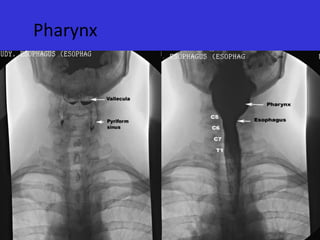

Pharynx